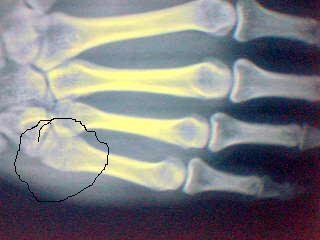

所谓“拳击手骨折”就是指掌骨颈骨折。骨折后掌骨通常向背侧成角。骨折后掌骨颈处通常肿胀、疼痛。所累及关节活动受限。也是我们手足科比较常见的骨折。